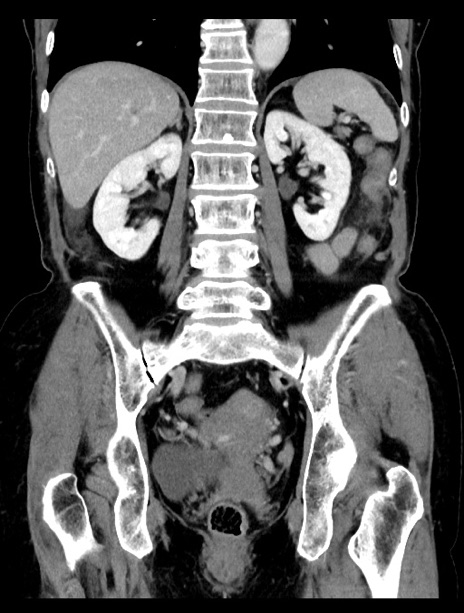

症例23(冠状断像)

【症例】70歳代女性

【主訴】下腹部痛・嘔吐

【現病歴】2日前より腹痛あり。昨日嘔吐あり。症状改善しないため来院。

【既往歴】胃GISTに対して胃部分切除後。

【身体所見】BT 37.1℃、BP 128/77mmHg、腹部:平坦・軟、下腹部に圧痛あり。

【データ】WBC 10200、CRP 0.31

横断像